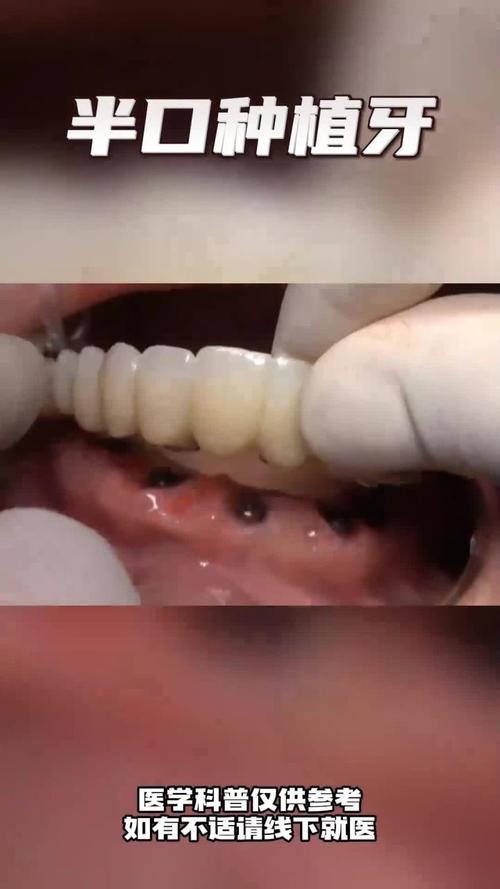

(四)牙冠修复(2-3周)

骨结合完成后,进入修复阶段:

- 取模:安装愈合基台,牙龈塑形1-2周后,用数字化扫描仪或传统硅橡胶取模,记录种植体位置、咬合关系及牙龈形态。

- 牙冠制作:根据模型加工牙冠,前牙牙冠多选用全瓷材料(如氧化锆、玻璃陶瓷),因其色泽通透、生物相容性好,可模拟天然牙的光学效果(如牙本质层、釉质层、切端半透明度)。

- 试戴与粘固:试戴牙冠,调整咬合、邻接关系及颜色,确认无误后用树脂水门汀粘固,完成最终修复。